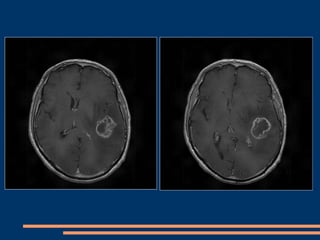

CAS CLINIQUES –GIESSEN+CHU FORT de FRANCE Patient de  35  ans  (GIESSEN) Ralentissement  psychomoteur depuis 1 mois , déficit moteur de l’hémicorps droit d’installation progressive , aphasie  de Wernicke et Broca. Juin 2009 : réalisation d’une IRM cérébrale montrant un glioblastome temporal profond gauche avec effet  de masse. Opéré avec GLIOLAN couplé au Pentero avec option fluoroscopie.

IRM pré-opératoire

IRM pré-opératoire (suite)